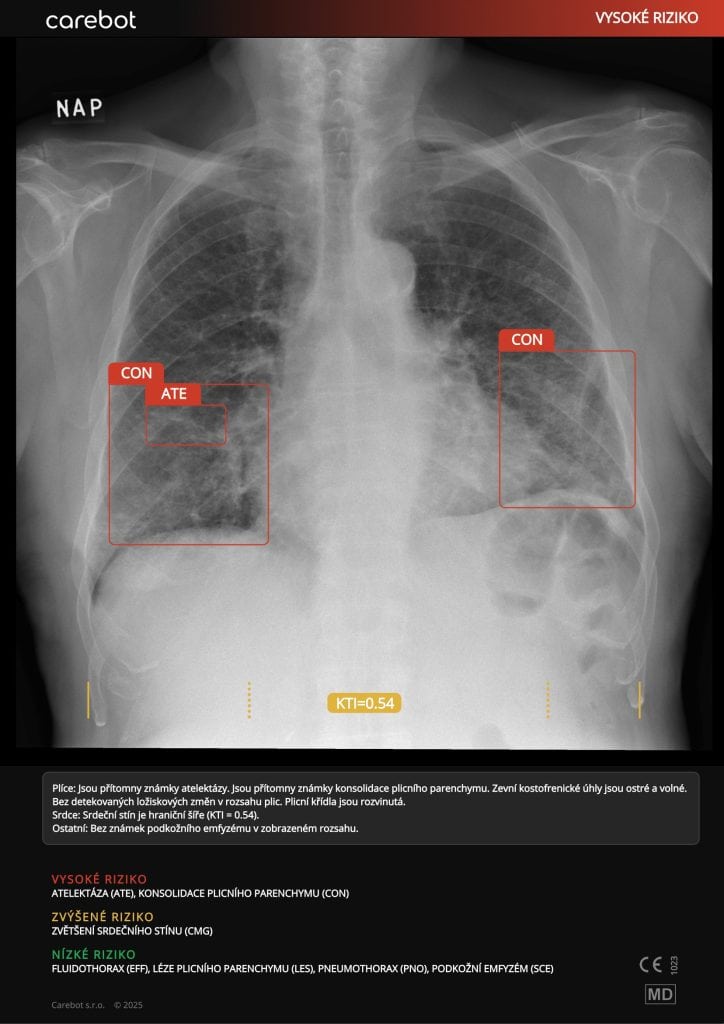

Carebot AI

Skupina AGEL rozširuje využívanie umelej inteligencie Carebot AI na automatickú analýzu röntgenových snímok hrudníka a kostí. Systém dokáže v priebehu niekoľkých sekúnd identifikovať viac než 60 typov nálezov, vrátane zápalov pľúc či zlomenín.

Carebot AI funguje ako „druhý pár očí“ – nehodnotí snímky namiesto lekára, ale upozorňuje na možné patologické oblasti.

Zvyšuje bezpečnosť pacienta, diagnostickú istotu a skracuje čas hodnotenia snímok až o 30 %. Pilotné nasadenie prebieha v Nemocnici AGEL Nový Jičín a ďalších zariadeniach s vysokým objemom vyšetrení. Podľa odborníkov ide o príklad zmysluplnej a praxe overenej implementácie umelej inteligencie v zdravotníctve. Systém je plne integrovaný do nemocničného PACS prostredia, čím odpadá potreba externého softvéru.